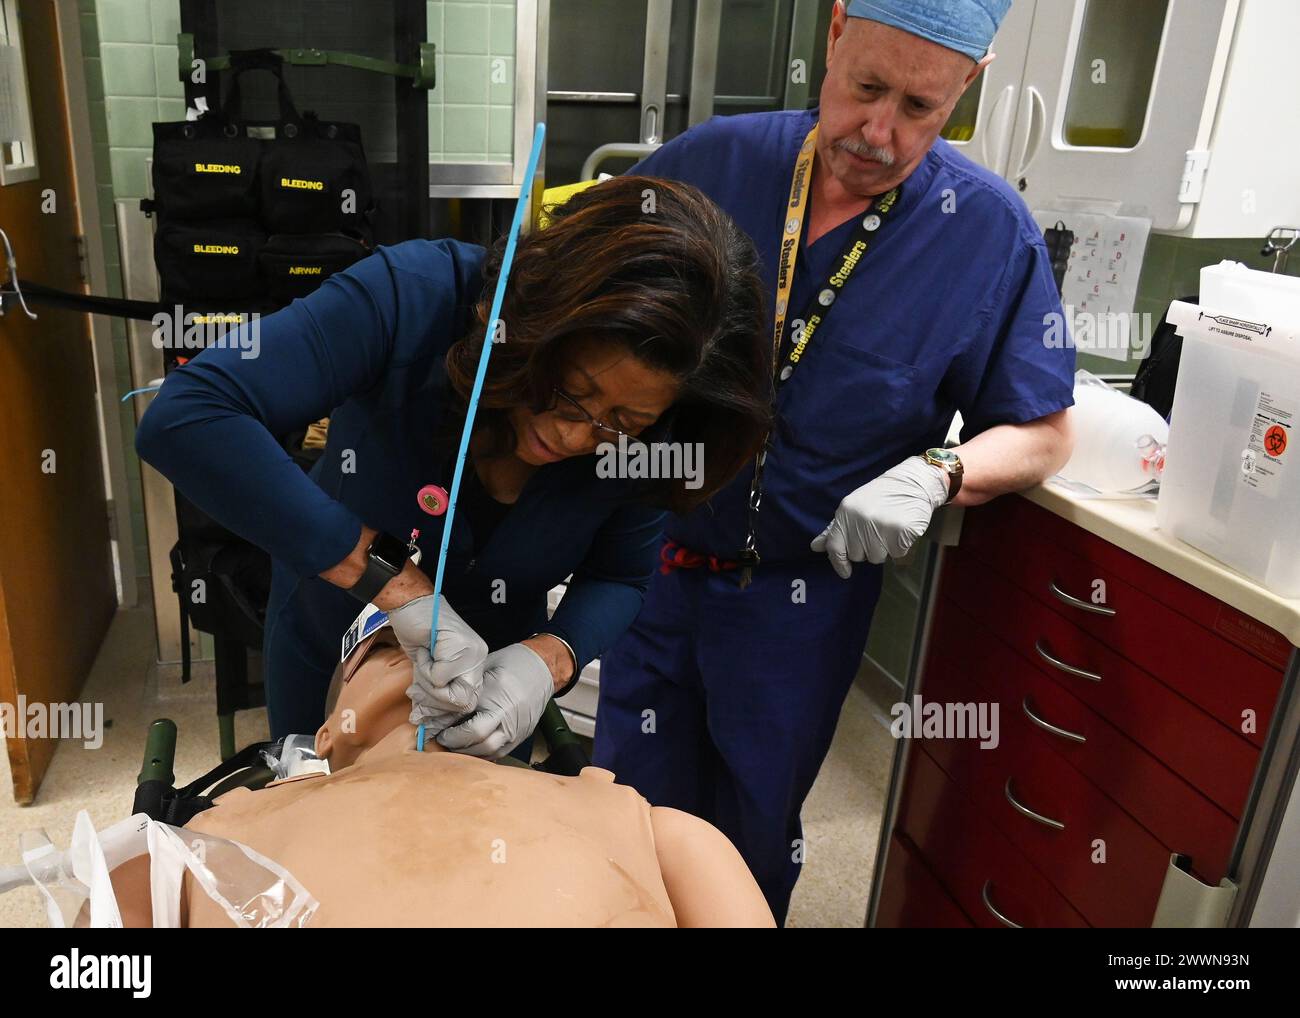

The Kimbrough Ambulatory Care Center Anesthesia Care Team simulated various methods of performing an emergency cricothyrotomy, Fort Meade, Maryland, Feb. 5, to validate providers' skills and update credentials. A cricothyrotomy is an incision made through the skin and cricothyroid membrane to establish a patent airway during certain life-threatening situations, such as airway obstruction by a foreign body, angioedema, or massive facial trauma. Defense Health Agency Stock Photohttps://www.alamy.com/image-license-details/?v=1https://www.alamy.com/the-kimbrough-ambulatory-care-center-anesthesia-care-team-simulated-various-methods-of-performing-an-emergency-cricothyrotomy-fort-meade-maryland-feb-5-to-validate-providers-skills-and-update-credentials-a-cricothyrotomy-is-an-incision-made-through-the-skin-and-cricothyroid-membrane-to-establish-a-patent-airway-during-certain-life-threatening-situations-such-as-airway-obstruction-by-a-foreign-body-angioedema-or-massive-facial-trauma-defense-health-agency-image600985198.html

The Kimbrough Ambulatory Care Center Anesthesia Care Team simulated various methods of performing an emergency cricothyrotomy, Fort Meade, Maryland, Feb. 5, to validate providers' skills and update credentials. A cricothyrotomy is an incision made through the skin and cricothyroid membrane to establish a patent airway during certain life-threatening situations, such as airway obstruction by a foreign body, angioedema, or massive facial trauma. Defense Health Agency Stock Photohttps://www.alamy.com/image-license-details/?v=1https://www.alamy.com/the-kimbrough-ambulatory-care-center-anesthesia-care-team-simulated-various-methods-of-performing-an-emergency-cricothyrotomy-fort-meade-maryland-feb-5-to-validate-providers-skills-and-update-credentials-a-cricothyrotomy-is-an-incision-made-through-the-skin-and-cricothyroid-membrane-to-establish-a-patent-airway-during-certain-life-threatening-situations-such-as-airway-obstruction-by-a-foreign-body-angioedema-or-massive-facial-trauma-defense-health-agency-image600985198.htmlRM2WWN6N2–The Kimbrough Ambulatory Care Center Anesthesia Care Team simulated various methods of performing an emergency cricothyrotomy, Fort Meade, Maryland, Feb. 5, to validate providers' skills and update credentials. A cricothyrotomy is an incision made through the skin and cricothyroid membrane to establish a patent airway during certain life-threatening situations, such as airway obstruction by a foreign body, angioedema, or massive facial trauma. Defense Health Agency

The Kimbrough Ambulatory Care Center Anesthesia Care Team simulated various methods of performing an emergency cricothyrotomy, Fort Meade, Maryland, Feb. 5, to validate providers' skills and update credentials. A cricothyrotomy is an incision made through the skin and cricothyroid membrane to establish a patent airway during certain life-threatening situations, such as airway obstruction by a foreign body, angioedema, or massive facial trauma. Defense Health Agency Stock Photohttps://www.alamy.com/image-license-details/?v=1https://www.alamy.com/the-kimbrough-ambulatory-care-center-anesthesia-care-team-simulated-various-methods-of-performing-an-emergency-cricothyrotomy-fort-meade-maryland-feb-5-to-validate-providers-skills-and-update-credentials-a-cricothyrotomy-is-an-incision-made-through-the-skin-and-cricothyroid-membrane-to-establish-a-patent-airway-during-certain-life-threatening-situations-such-as-airway-obstruction-by-a-foreign-body-angioedema-or-massive-facial-trauma-defense-health-agency-image600985589.html

The Kimbrough Ambulatory Care Center Anesthesia Care Team simulated various methods of performing an emergency cricothyrotomy, Fort Meade, Maryland, Feb. 5, to validate providers' skills and update credentials. A cricothyrotomy is an incision made through the skin and cricothyroid membrane to establish a patent airway during certain life-threatening situations, such as airway obstruction by a foreign body, angioedema, or massive facial trauma. Defense Health Agency Stock Photohttps://www.alamy.com/image-license-details/?v=1https://www.alamy.com/the-kimbrough-ambulatory-care-center-anesthesia-care-team-simulated-various-methods-of-performing-an-emergency-cricothyrotomy-fort-meade-maryland-feb-5-to-validate-providers-skills-and-update-credentials-a-cricothyrotomy-is-an-incision-made-through-the-skin-and-cricothyroid-membrane-to-establish-a-patent-airway-during-certain-life-threatening-situations-such-as-airway-obstruction-by-a-foreign-body-angioedema-or-massive-facial-trauma-defense-health-agency-image600985589.htmlRM2WWN771–The Kimbrough Ambulatory Care Center Anesthesia Care Team simulated various methods of performing an emergency cricothyrotomy, Fort Meade, Maryland, Feb. 5, to validate providers' skills and update credentials. A cricothyrotomy is an incision made through the skin and cricothyroid membrane to establish a patent airway during certain life-threatening situations, such as airway obstruction by a foreign body, angioedema, or massive facial trauma. Defense Health Agency

The Kimbrough Ambulatory Care Center Anesthesia Care Team simulated various methods of performing an emergency cricothyrotomy, Fort Meade, Maryland, Feb. 5, to validate providers' skills and update credentials. A cricothyrotomy is an incision made through the skin and cricothyroid membrane to establish a patent airway during certain life-threatening situations, such as airway obstruction by a foreign body, angioedema, or massive facial trauma. Defense Health Agency Stock Photohttps://www.alamy.com/image-license-details/?v=1https://www.alamy.com/the-kimbrough-ambulatory-care-center-anesthesia-care-team-simulated-various-methods-of-performing-an-emergency-cricothyrotomy-fort-meade-maryland-feb-5-to-validate-providers-skills-and-update-credentials-a-cricothyrotomy-is-an-incision-made-through-the-skin-and-cricothyroid-membrane-to-establish-a-patent-airway-during-certain-life-threatening-situations-such-as-airway-obstruction-by-a-foreign-body-angioedema-or-massive-facial-trauma-defense-health-agency-image600985568.html

The Kimbrough Ambulatory Care Center Anesthesia Care Team simulated various methods of performing an emergency cricothyrotomy, Fort Meade, Maryland, Feb. 5, to validate providers' skills and update credentials. A cricothyrotomy is an incision made through the skin and cricothyroid membrane to establish a patent airway during certain life-threatening situations, such as airway obstruction by a foreign body, angioedema, or massive facial trauma. Defense Health Agency Stock Photohttps://www.alamy.com/image-license-details/?v=1https://www.alamy.com/the-kimbrough-ambulatory-care-center-anesthesia-care-team-simulated-various-methods-of-performing-an-emergency-cricothyrotomy-fort-meade-maryland-feb-5-to-validate-providers-skills-and-update-credentials-a-cricothyrotomy-is-an-incision-made-through-the-skin-and-cricothyroid-membrane-to-establish-a-patent-airway-during-certain-life-threatening-situations-such-as-airway-obstruction-by-a-foreign-body-angioedema-or-massive-facial-trauma-defense-health-agency-image600985568.htmlRM2WWN768–The Kimbrough Ambulatory Care Center Anesthesia Care Team simulated various methods of performing an emergency cricothyrotomy, Fort Meade, Maryland, Feb. 5, to validate providers' skills and update credentials. A cricothyrotomy is an incision made through the skin and cricothyroid membrane to establish a patent airway during certain life-threatening situations, such as airway obstruction by a foreign body, angioedema, or massive facial trauma. Defense Health Agency

The Kimbrough Ambulatory Care Center Anesthesia Care Team simulated various methods of performing an emergency cricothyrotomy, Fort Meade, Maryland, Feb. 5, to validate providers' skills and update credentials. A cricothyrotomy is an incision made through the skin and cricothyroid membrane to establish a patent airway during certain life-threatening situations, such as airway obstruction by a foreign body, angioedema, or massive facial trauma. Defense Health Agency Stock Photohttps://www.alamy.com/image-license-details/?v=1https://www.alamy.com/the-kimbrough-ambulatory-care-center-anesthesia-care-team-simulated-various-methods-of-performing-an-emergency-cricothyrotomy-fort-meade-maryland-feb-5-to-validate-providers-skills-and-update-credentials-a-cricothyrotomy-is-an-incision-made-through-the-skin-and-cricothyroid-membrane-to-establish-a-patent-airway-during-certain-life-threatening-situations-such-as-airway-obstruction-by-a-foreign-body-angioedema-or-massive-facial-trauma-defense-health-agency-image600987065.html

The Kimbrough Ambulatory Care Center Anesthesia Care Team simulated various methods of performing an emergency cricothyrotomy, Fort Meade, Maryland, Feb. 5, to validate providers' skills and update credentials. A cricothyrotomy is an incision made through the skin and cricothyroid membrane to establish a patent airway during certain life-threatening situations, such as airway obstruction by a foreign body, angioedema, or massive facial trauma. Defense Health Agency Stock Photohttps://www.alamy.com/image-license-details/?v=1https://www.alamy.com/the-kimbrough-ambulatory-care-center-anesthesia-care-team-simulated-various-methods-of-performing-an-emergency-cricothyrotomy-fort-meade-maryland-feb-5-to-validate-providers-skills-and-update-credentials-a-cricothyrotomy-is-an-incision-made-through-the-skin-and-cricothyroid-membrane-to-establish-a-patent-airway-during-certain-life-threatening-situations-such-as-airway-obstruction-by-a-foreign-body-angioedema-or-massive-facial-trauma-defense-health-agency-image600987065.htmlRM2WWN93N–The Kimbrough Ambulatory Care Center Anesthesia Care Team simulated various methods of performing an emergency cricothyrotomy, Fort Meade, Maryland, Feb. 5, to validate providers' skills and update credentials. A cricothyrotomy is an incision made through the skin and cricothyroid membrane to establish a patent airway during certain life-threatening situations, such as airway obstruction by a foreign body, angioedema, or massive facial trauma. Defense Health Agency